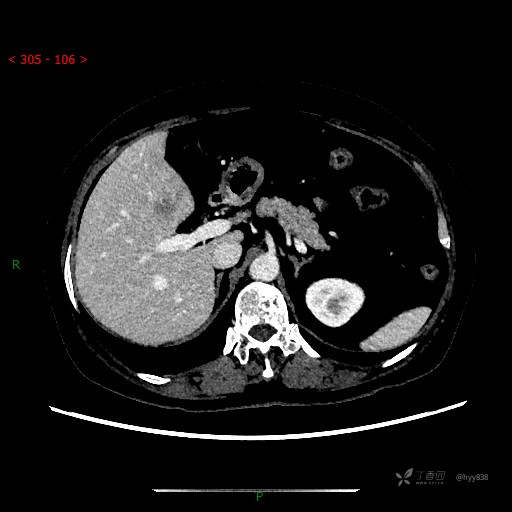

静脉期